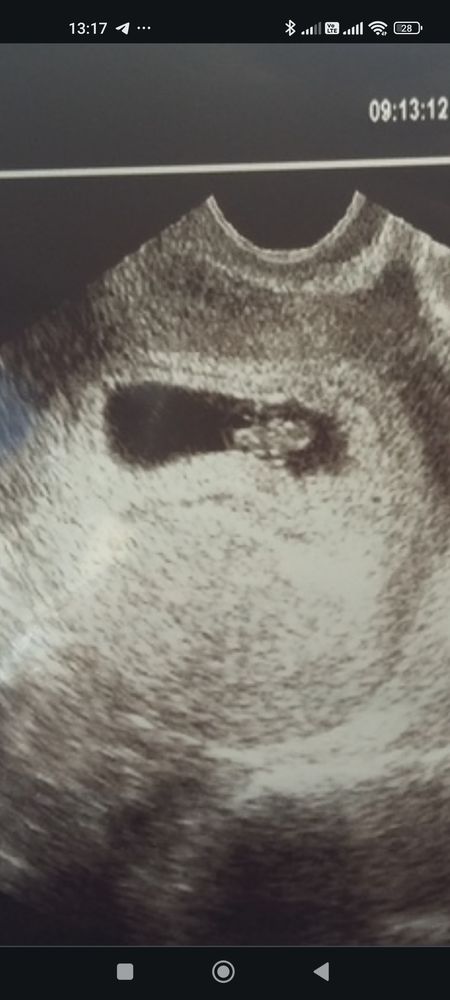

Виктория , вот тут кажись получше видно. Вчера в принципе сказали, что лялечка уже начала появляться, но пока сложно дифференцируема. Жду воскресенья с трепетом 🫣 Изображение